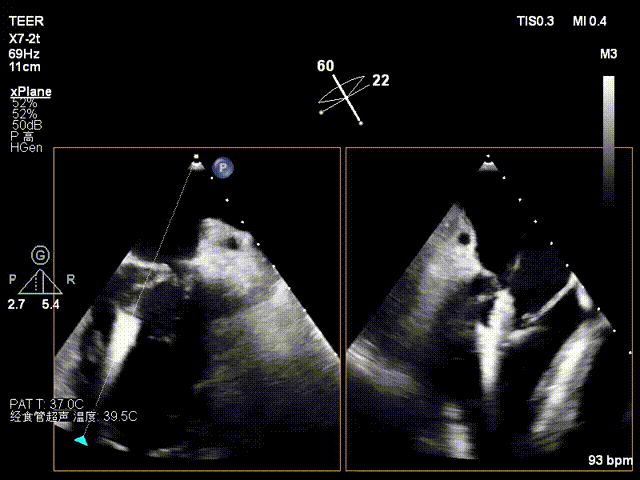

X-plane 1区

X-plane 2区

经食道超声检查提示:二尖瓣瓣叶增厚冗长2区后瓣脱垂呈连枷样改变,考虑Barlow’s综合征。评估解剖结构:前叶长度:3.3cm,后叶长度:2.8cm,脱垂宽度:26mm,脱垂高度:19mm,瓣口面积:7.5cm²。